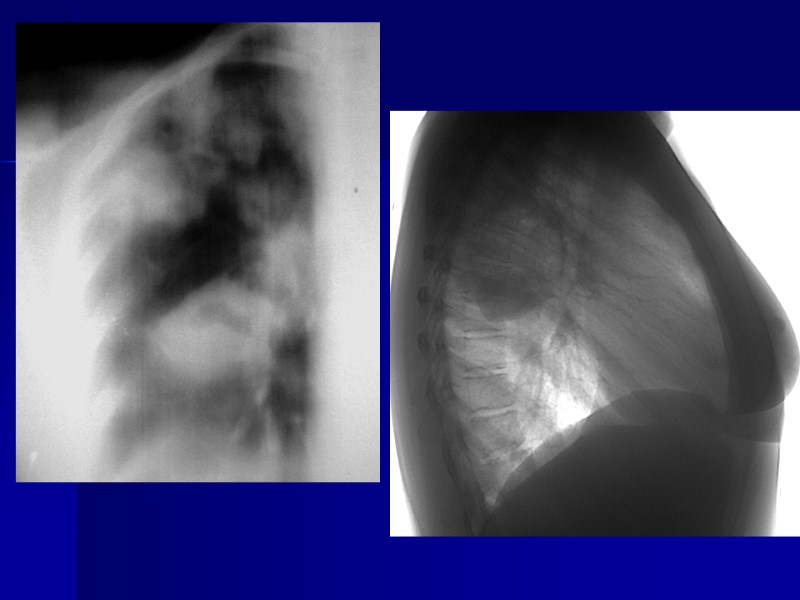

Сочетание инфильтративного туберкулеза верхней доли справа с распадом и туберкулем S6 легких